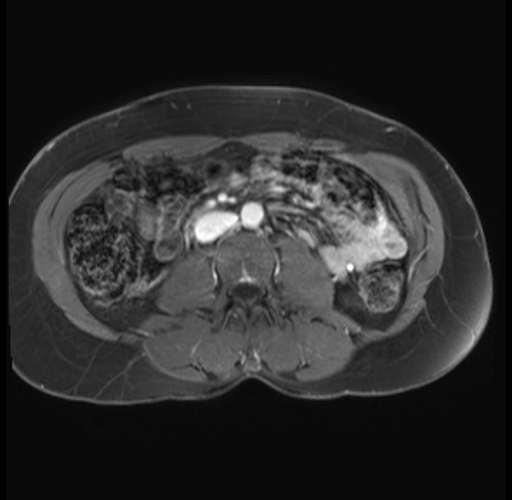

Imaging Analysis

Look through the patient's CT scan to identify any areas of concern for the necessary procedure.

Based on your CT findings, which issue(s) are present and would give reason for "planned slowing down moment(s)" in this case?

Considering a standard distal pancreatectomy procedure, what step(s) of the operation would you do differently in this case?